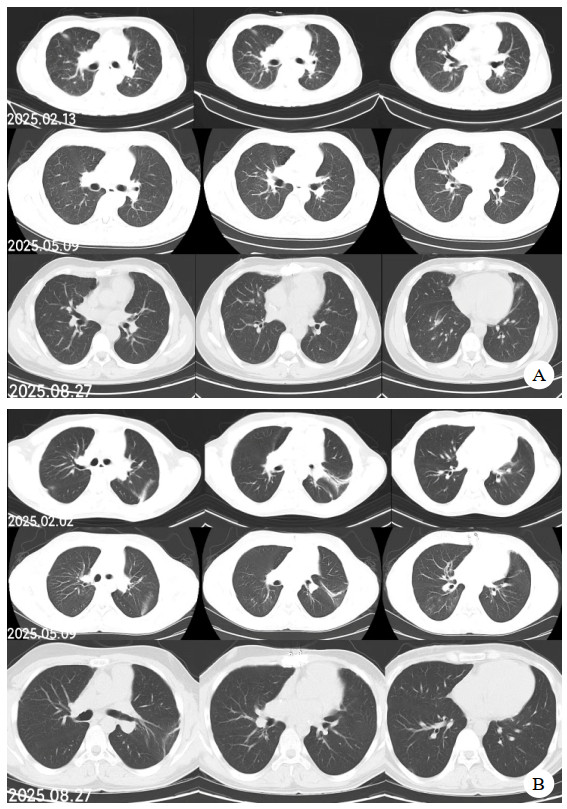

同时给予镇痛、镇静联合肌松,去甲肾上腺素泵入维持血压,俯卧位通气,B某入院后出现高热,经验性给予美罗培南联合万古霉素抗感染治疗,后降阶梯调整为哌拉西林他唑巴坦联合万古霉素治疗;C某抗感染方案为经验性使用万古霉素联合哌拉西林他唑巴坦治疗,痰培养出鲍曼不动杆菌后改为替加环素、头孢哌酮舒巴坦及万古霉素治疗;根据《刺激性气体中毒诊治专家共识》[5]中关于重症患者的治疗措施,同时给予2人泮托拉唑抑酸护胃,氨溴索、富露施化痰、甲泼尼龙抗炎、西维来司他纳及乌司他丁清除炎性介质,维生素C抗氧化、保肝、输血补液,纤支镜吸痰及肺泡灌洗,维持水电解质平衡及营养支持治疗,特别考虑到肺损伤情况,在使用有创通气时给予超保护性通气策略[5, 7];2人仍先后出现气胸、纵膈气肿,行胸腔闭式引流;持续V-V ECMO治疗15 d后,肺部纤维化不可逆转,高分辨率CT肺纤维化评分 > 75%(图 3、4),符合终末期肺病标准,有肺移植指征[8],经评估后2人顺利完成病变肺组织切除(图 5),双侧序贯肺移植,术后患者复查胸片肺部恢复正常(图 6),2位患者术后气管切管接呼吸机辅助通气,并给予泼尼松、他克莫司、吗替麦考酚酯抗排异治疗,其余根据病情给予万古霉素调节肠道菌群、抗感染、保肝、抗凝、呼吸康复锻炼等治疗,后顺利脱机、拔除气切套管,病情稳定出院,后续规律复查胸部CT(图 7)恢复良好。

| 注:图A为B某;图B为C某 图 7 肺移植术后第2个月、5个月、8个月CT影像 |